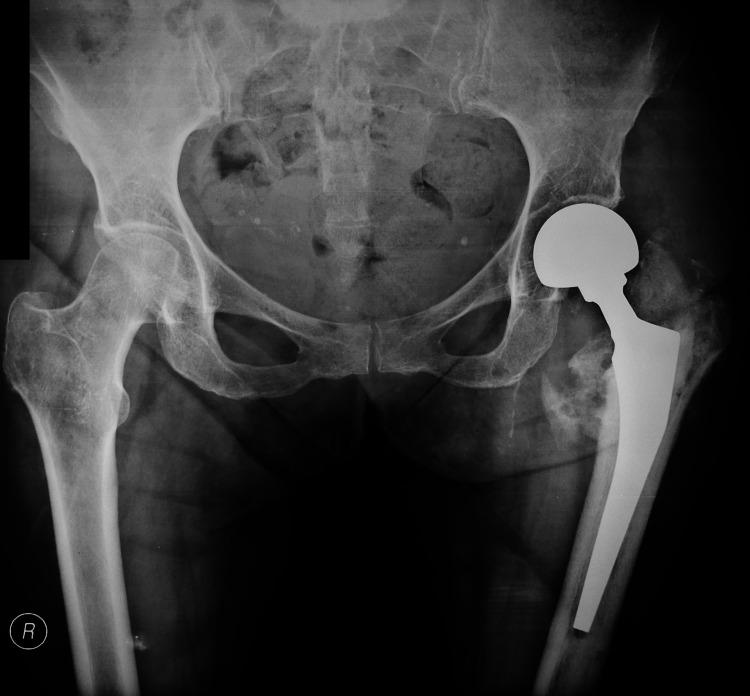

Intramedullary nailing is an established method for treating pertrochanteric fractures. However, the widespread use of this technique comes along with a variety of complications. We present a case of a 50-year-old female who presented to the emergency department suffering a left pertrochanteric fracture. She was treated with proximal femoral nailing and discharged home. Nine months later, she presented again to the emergency department with pain and an inability to bear weight. Imaging revealed the mechanical failure of the hip screw and loss of fracture fixation. Revision surgery included extraction of the broken hardware and a left hip hemiarthroplasty. The removed implant was sent for further evaluation. Fractographic analysis showed acute breakage due to bending and torsion forces acting on the screw with no relevant signs of metal fatigue. This biomechanical method is of great value for the surgeon and the implant manufacturer in order to understand the failure pattern and optimize future implants and fixation techniques. Improved implant biomechanical properties together with meticulous surgical technique constitute the cornerstones for optimal results.

髓内钉固定术是治疗转子间骨折的一种成熟方法。然而,这项技术的广泛应用伴随着各种并发症。我们报告一例50岁女性,因左侧转子间骨折就诊于急诊科。她接受了股骨近端钉固定治疗后出院回家。九个月后,她再次因疼痛和无法负重就诊于急诊科。影像学检查显示髋螺钉出现机械故障,骨折固定失效。翻修手术包括取出断裂的内固定器械并进行左侧髋关节半关节置换术。取出的植入物送去做进一步评估。断口分析显示,螺钉因弯曲和扭转力导致急性断裂,无明显金属疲劳迹象。这种生物力学方法对于外科医生和植入物制造商理解失效模式以及优化未来的植入物和固定技术具有重要价值。改善植入物的生物力学性能并辅以细致的手术技术是取得最佳效果的基石。